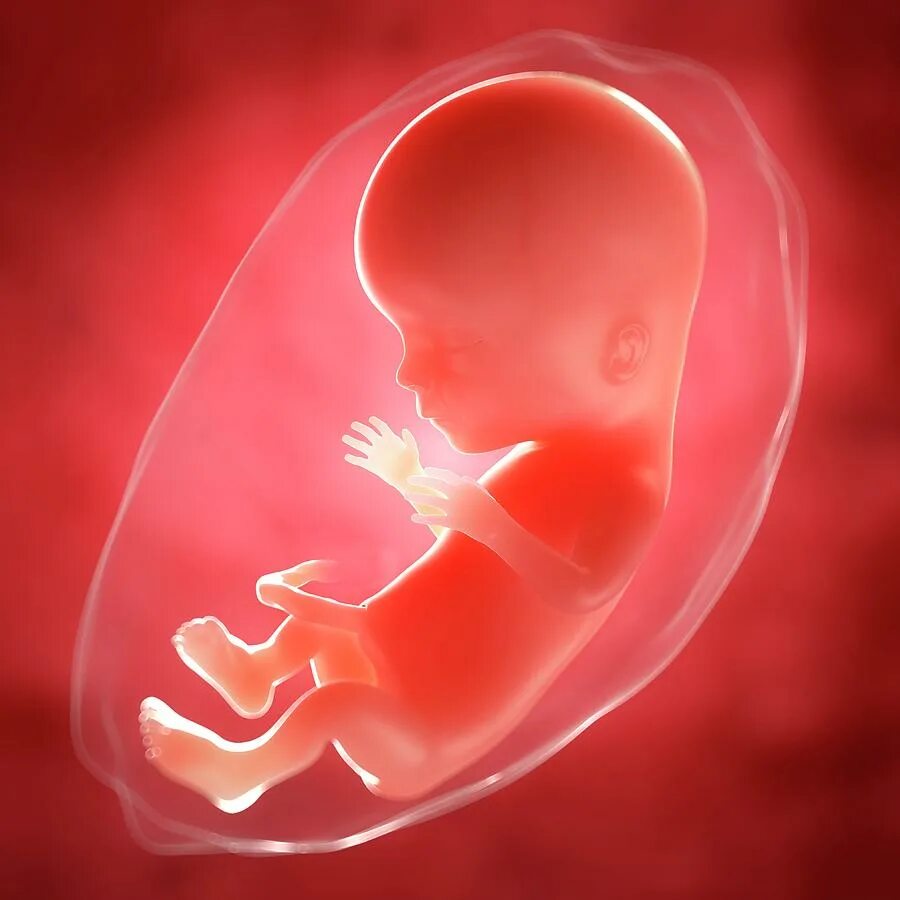

Беременность 15 недель развитие плода и ощущения